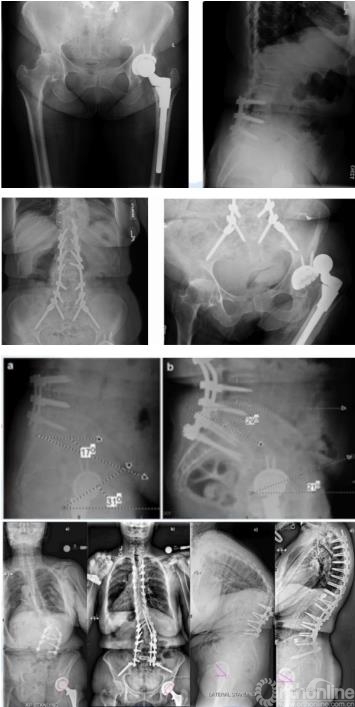

强直性脊柱炎对THA的影响

强直性脊柱炎(AS)患者脊柱矢状面的畸形,会导致胸椎后凸增大,腰椎前凸减小,这样的生理结构导致患者站立位骨盆出现过度后倾。系统综述也显示,这样的后倾导致髋臼前倾角异常增大。骨盆后倾,髋关节前倾角增大也是THA术后脱位和翻修的主要原因。因此针对AS患者,术前需要设计髋臼假体位置。

图7 AS引起THA术后脱位病例

手术时可根据后倾角度调整髋臼假体置入角度,减小外展与前倾角,防止术后脱位,增加站立位髋关节稳定性的同时,减少了假体与骨的接触面积,以适应变化的脊柱-骨盆力线,避免术后出现髋臼假体过度前倾,以及站立位时发生后方撞击、前方不稳甚至前脱位等并发症。对于合并脊柱后凸畸形的AS患者,除非畸形过于严重,应首选脊柱矫形术,再行THA。